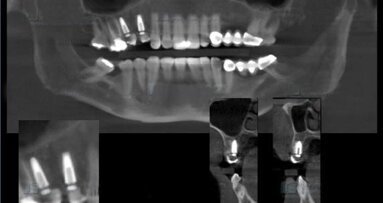

Paciente que presenta zona edéntula en pieza dentaria 2.5 y 2.6, por lo que se evalúa para la posible colocación de un implante dental en zona del 25 para evitar perforación del seno maxilar, puesto que el paciente no quería procedimientos complejos.

Figura 2. Se realiza una tomografía Cone Beam con la guía puesta en boca del paciente.